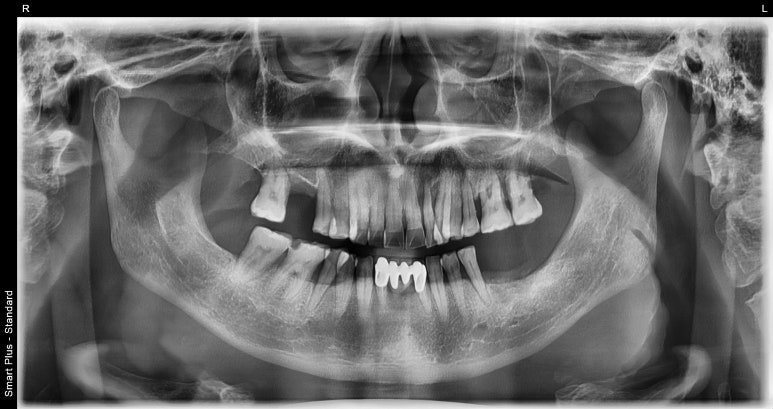

임플란트브릿지 치료전

2023-03-24

기존 환자분의 당부의 말씀과 함께 내원해주신 환자분은 보시는 바와 같이

왼쪽 아래 어금니 3개, 오른쪽 위 어금니 1개를 이미 상실하신 상태에서 내원해 주셨습니다.

우선 우리 환자분 가장 시급한 치료는 왼쪽 아래 어금니 부분이었는데요.

아무래도 치아가 3개 결손되어있다보니 이대로 계속해서 방치할 경우

위아래 맞물리는 치아가 없어 상악 어금니가 점점 아래쪽으로 이동할 가능성이 있고,

그렇게 되면 치아 상태는 더 안좋아져 식사하는데 큰 불편함이 있을 수 있기 때문에 빠르게 임플란트로 치료 계획을 세웠습니다.

아울러 왼쪽 아래부분 임플란트 식립하기에 잇몸뼈의 양이나 높이가 충분하지 않은 것으로 판단해

뼈이식도 함께 진행하고 3개월 후에 최종 보철물까지 올라가는 것으로 일정을 잡았습니다.